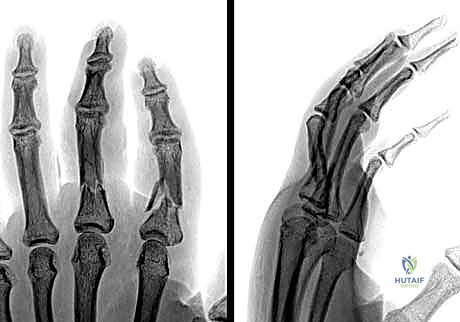

يُستخدم العلاج التحفظي للكسور المستقرة، غير المنزاحة، والتي لا تعاني من أي تشوه دوراني.

- التثبيت بجبيرة (Splinting): يتم تثبيت الإصبع أو اليد في وضعية تُعرف بـ "الوضعية الآمنة" (Safe Position أو James Position). في هذه الوضعية، يتم ثني المفاصل السنعية السلامية (MCP) بزاوية 70-90 درجة، وتُترك المفاصل بين السلامية (PIP و DIP) في وضعية المد الكامل (0 درجة). هذا الوضع يحافظ على طول الأربطة الجانبية ويمنع تيبس المفاصل.

- التثبيت بالشريط اللاصق (Buddy Taping): في الكسور البسيطة جداً، يتم ربط الإصبع المصاب بالإصبع السليم المجاور له. يعمل الإصبع السليم كجبيرة ديناميكية طبيعية تسمح بالحركة المبكرة وتمنع التيبس.

- المتابعة الدورية: يتطلب العلاج التحفظي إجراء أشعة سينية أسبوعية خلال الأسابيع الثلاثة الأولى للتأكد من عدم انزياح الكسر من مكانه.

1. الرد المغلق والتثبيت بأسلاك كيرشنر (CRPP - Closed Reduction and Percutaneous Pinning):

تُعد هذه الطريقة الأقل توغلاً. يقوم الدكتور هطيف برد الكسر يدوياً تحت توجيه جهاز الأشعة السينية المباشر (C-arm) في غرفة العمليات، ثم يقوم بإدخال أسلاك معدنية دقيقة (K-wires) عبر الجلد لتثبيت العظم.

* المزايا: لا تتطلب شقاً جراحياً كبيراً، تحافظ على الإمداد الدموي للعظم، وتقلل من خطر التصاقات الأوتار.

* العيوب: تتطلب إبقاء جزء من السلك خارج الجلد (عادةً)، مما يستلزم إزالتها في العيادة بعد 4-6 أسابيع.